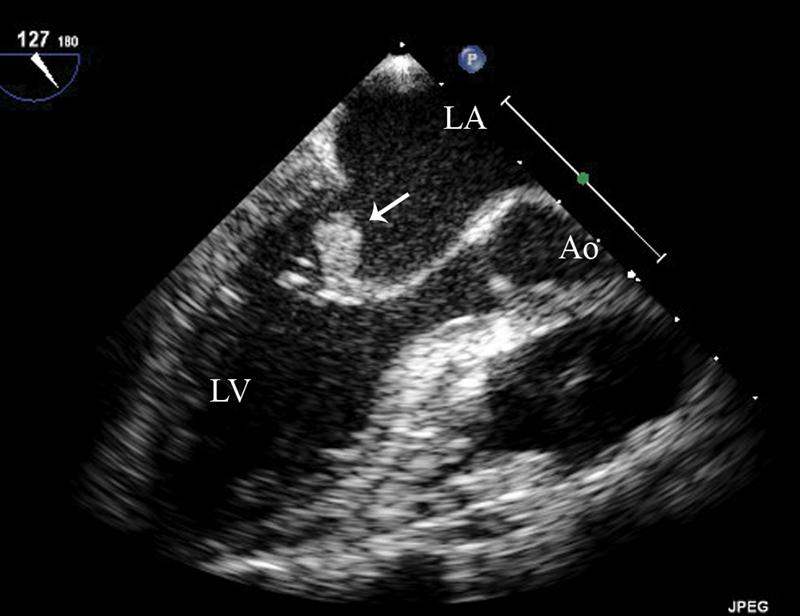

فحوصات تشخيصية لبعض امراض القلب والشرايين التاجية